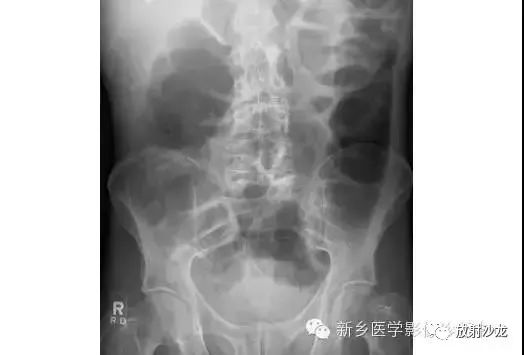

腹痛患者所做的腹部平片。有助于临床诊断的微妙征象是什么呢?

气腹患者摩里逊陷凹存在气体。平片中,靠近11肋的右上象限可见三角形(如在这种情况下)、半圆形,或月牙形的气体集聚。在仰卧位X光片中,右上象限的气体不能解释为肠道内气体,通常为腹腔内游离气体的最早迹象。

同一患者前-后坐位的胸片所示右膈下(箭头)游离气体,证实了气腹的诊断。